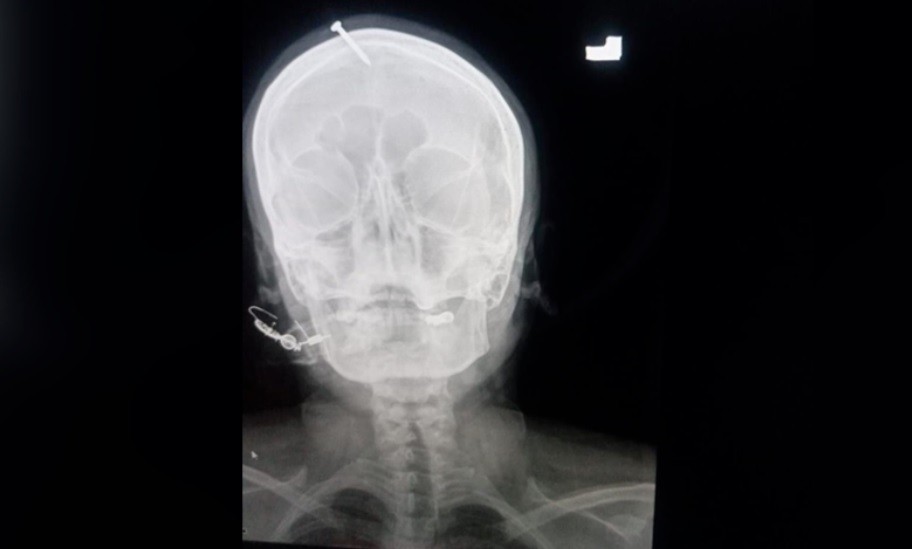

Una radiografía mostró que el clavo había sido clavado cinco centímetros en el cráneo, sin llegar al cerebro.